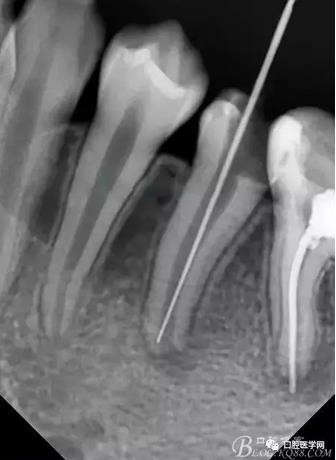

在拔髓的過程中遇到流血,但是不會(huì)疼,根管腔超級(jí)大,40#根管挫完全不用加壓就直接掉到根尖部,測(cè)長直接報(bào)警,嚇了一跳,根尖孔這么大,40#根管挫很輕松就超出根尖孔。

擔(dān)心超出根尖孔破壞根尖組織,及時(shí)測(cè)長再加一張X片,如下圖:

小心翼翼的控制根管長度后進(jìn)行根管預(yù)備,3%雙氧水與生理鹽水交替沖洗,吸潮紙尖吸干,行氫氧化鈣根管充填,氧化鋅丁香油暫封,醫(yī)囑2周復(fù)診。